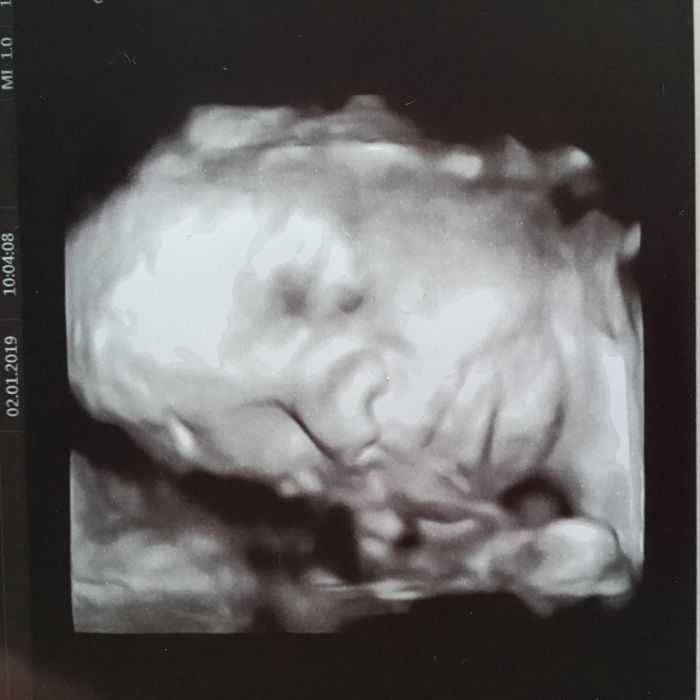

Zrzko krasna fotecka

Floras, tak to jsou skvělý zprávy!!! Teď už to jenom vydržet ale už to utece :) Já mám za sebou taky kontrolu a prcina se tam má úplně báječně a všechno je v pořádku :)